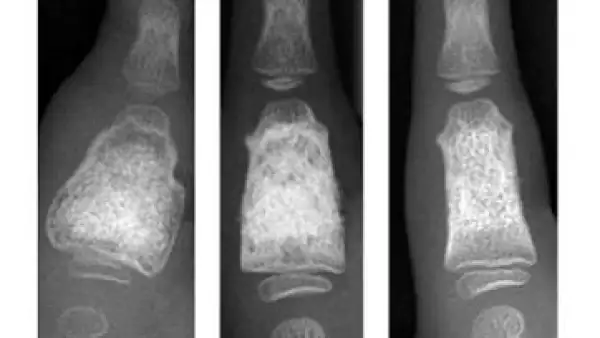

“La impresión 3D se utiliza en el área médica para hacer prototipos de piezas, pero aun no se cuenta con los materiales y la tecnología adecuada para que puedan ir dentro del cuerpo. Es decir, se toma una radiografía de la parte que necesita ser sustituida o implantada en una persona, se hace el prototipo en 3D y de ahí se manda a fabricar en titanio o algún otro material que sí esté aprobado para ser usado dentro del cuerpo. Existe esa desinformación, pero nosotros solo ofrecemos prototipos de plástico”, precisó Rubén Muñoz.